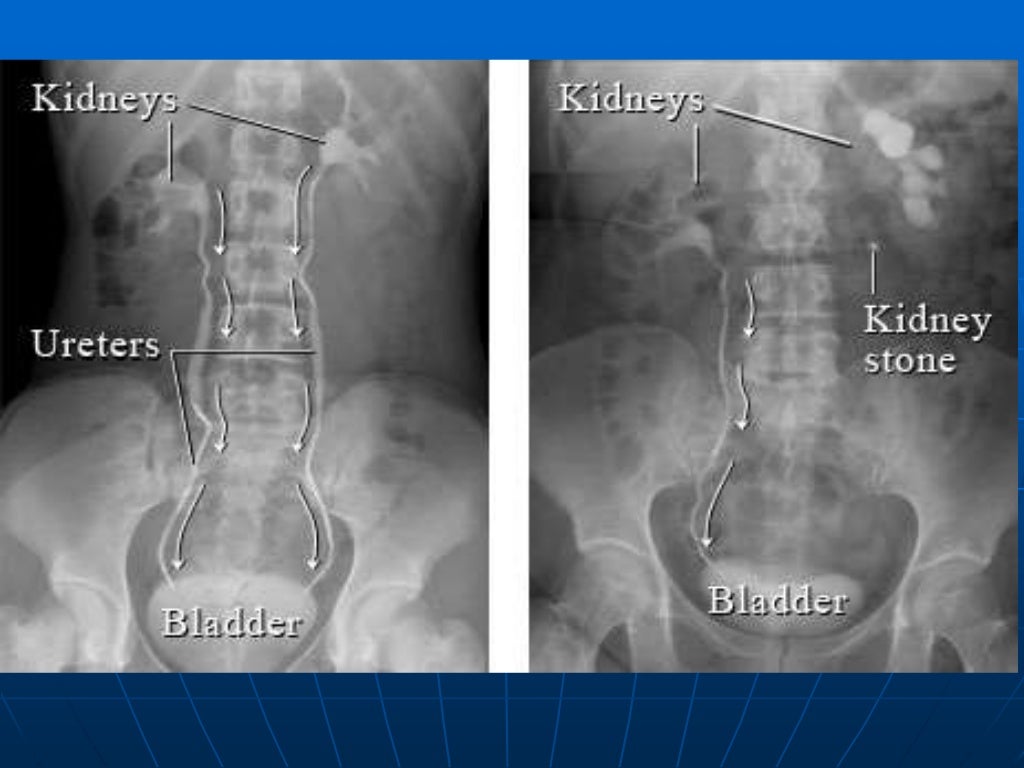

Low Back Pain with a normal xray Low Back Pain X Ray Guidelines The american college of physicians and the american pain society classify lbp into the following broad categories: American college of radiology acr appropriateness criteria® low back pain. Identify persons at risk for chronic disability and intervene early; The evaluation for low back pain should include a complete, focused medical history looking for red flags, which include, but are not limited. Low Back Pain X Ray Guidelines.

Low Back Pain with a normal xray Low Back Pain X Ray Guidelines Acute low back pain with or without. This guideline covers assessing and managing low back pain and sciatica in people aged 16 and over. The evaluation for low back pain should include a complete, focused medical history looking for red flags, which include, but are not limited to:. Identify persons at risk for chronic disability and intervene early; American college. Low Back Pain X Ray Guidelines.